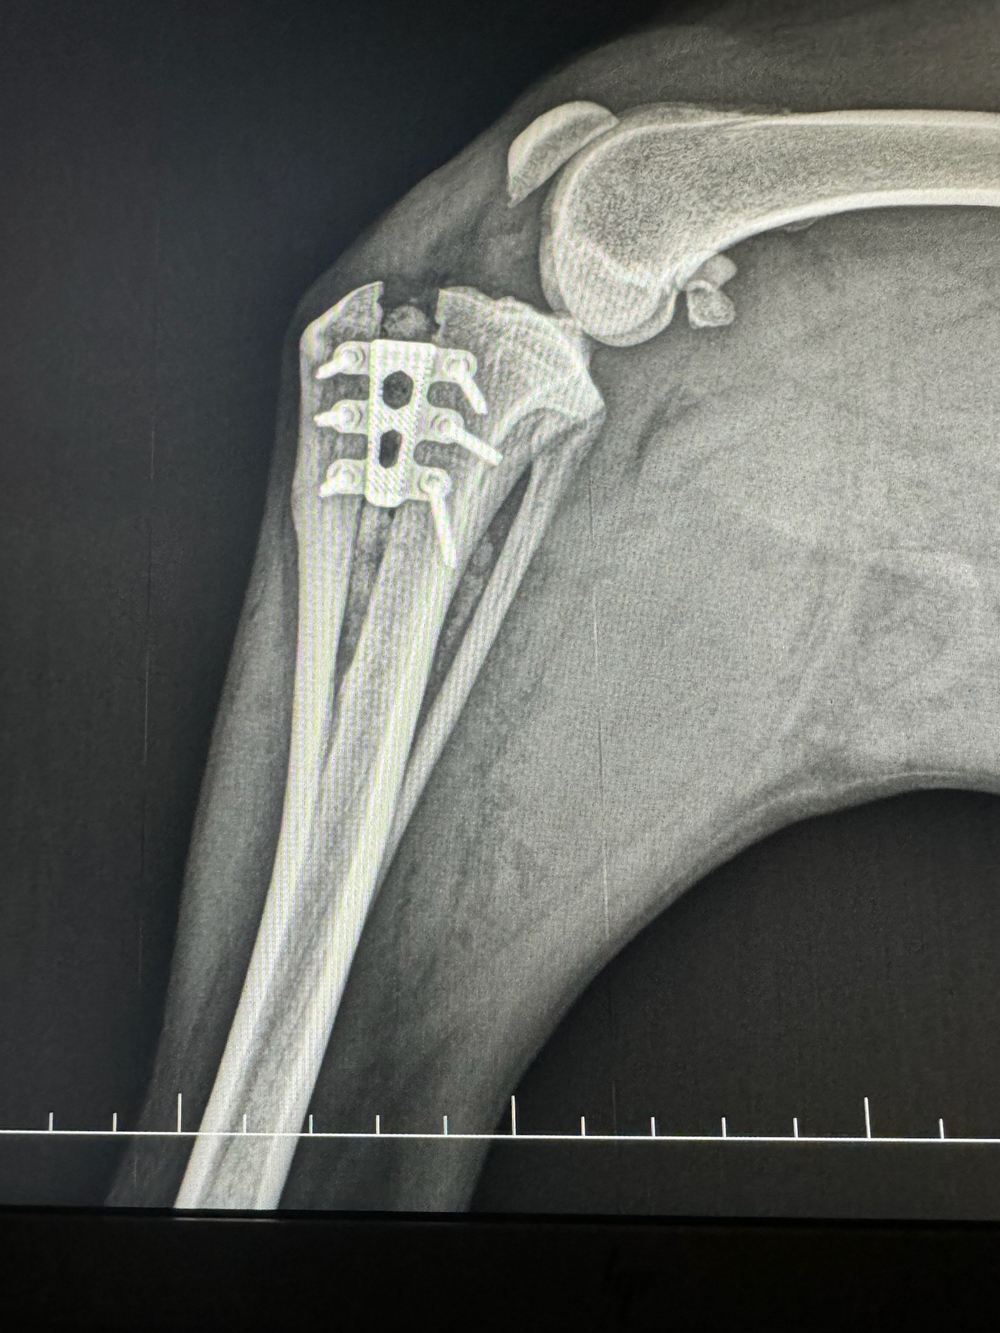

La radiographie vétérinaire est une technique d’imagerie médicale qui permet de visualiser les os, les organes internes, les tissus mous et toutes les structures internes du corps des animaux. Les radiographies vétérinaires sont couramment utilisées pour diagnostiquer des fractures, des maladies pulmonaires, des problèmes cardiaques, des obstructions intestinales, des tumeurs, et bien d’autres affections.

C’est un outil précieux pour notre équipe vétérinaire afin d’établir un diagnostic précis, et planifier un traitement adapté pour vos chiens, chats et Nacs.